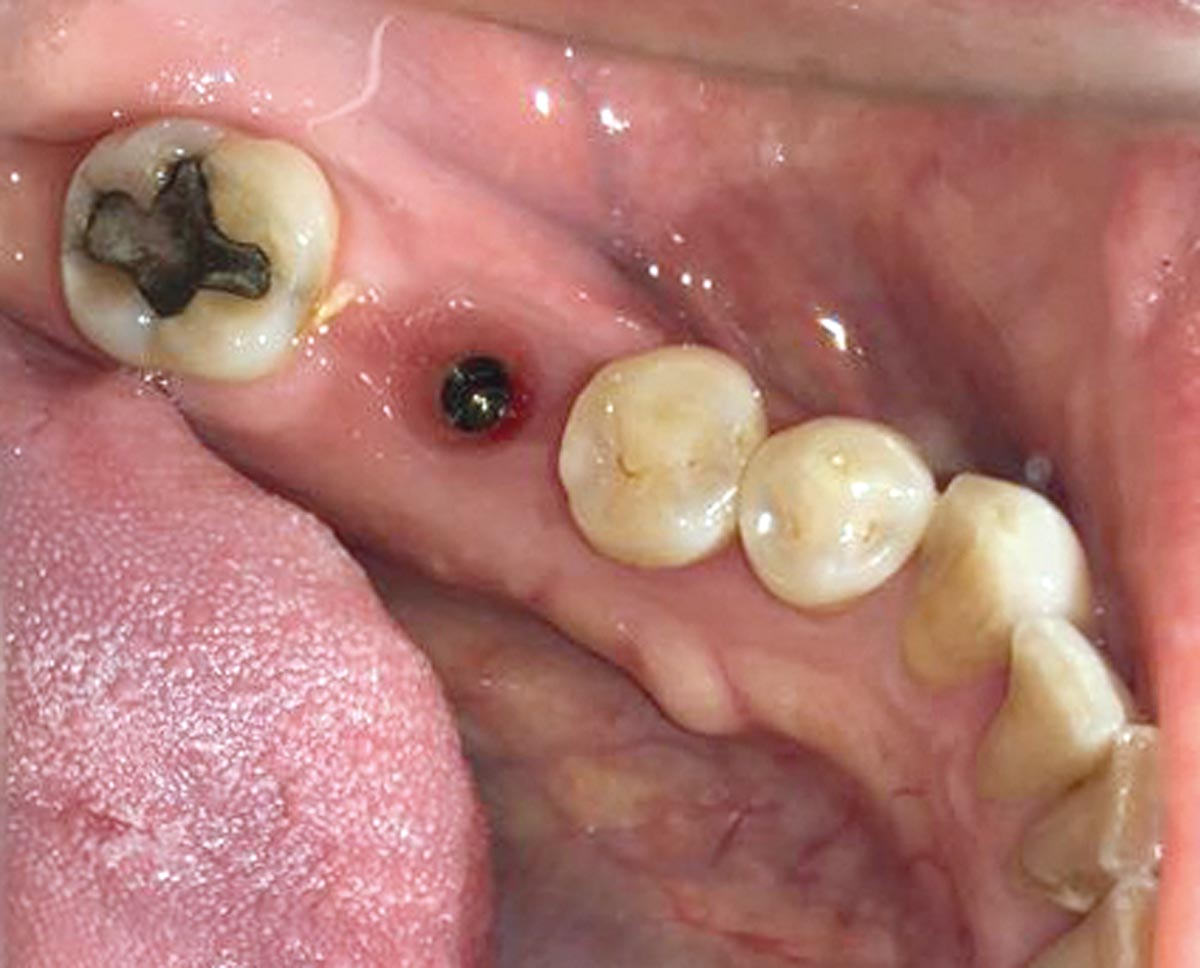

6/19 - Socket after extraction of tooth 4.6

Immediate implant placement using maxresorb® - Dr. Alejandro Signorio